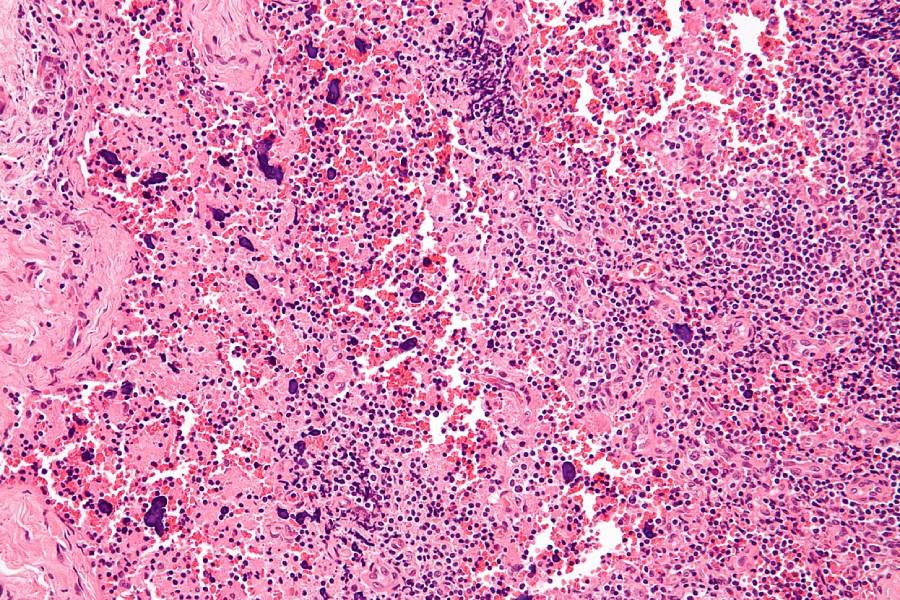

Изменения лимфатического узла, вызванные системной красной волчанкой Фото: wikipedia.org